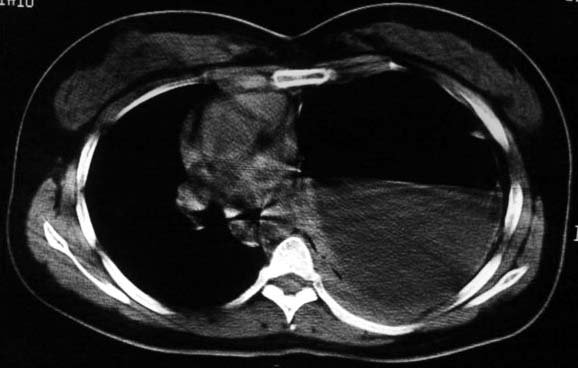

标题: CT5517:女性、24岁,反复胸痛、气促不能平卧半月。

左肺可见二个含气或液气的囊状影,左肺段支气管、左肺动脉显示不清,纵隔右移,考虑:左肺支气管肺囊肿,左肺发育不良,纵隔疝。

综合分析考虑:1左侧包裹性液气胸。2左侧胸膜肥厚。3左肺膨胀不全

液气胸 怎么会有2 个大腔?

左肺发育不良、支气管囊肿 应该纵隔左移的多吧

还是个膈疝